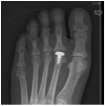

- Resurfacing of 2nd Metatarsal

- Uses include OA, AVN, Freiberg disease